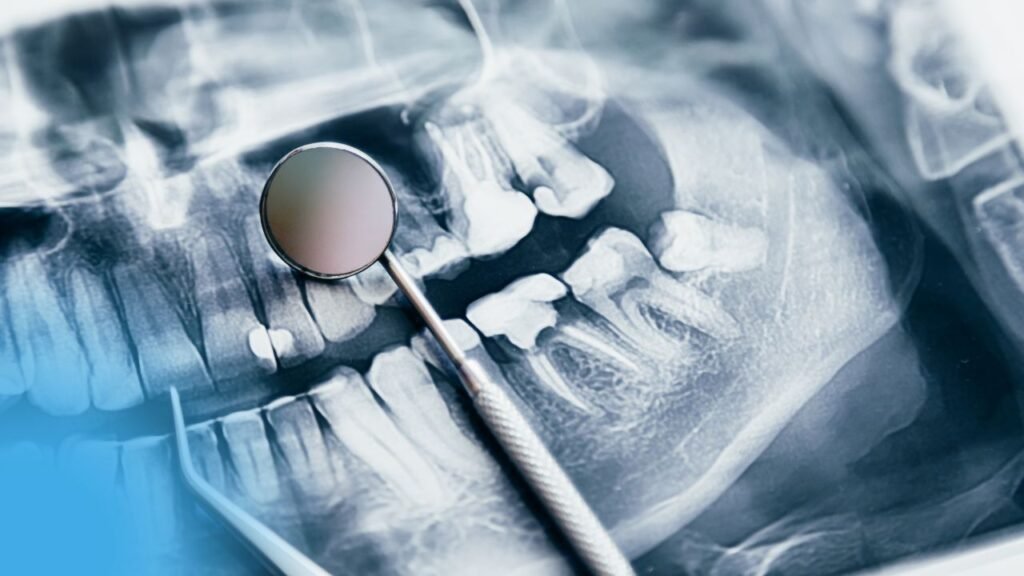

LES ÉTIOLOGIES DES ANOMALIES DENTO MAXILLO-FACIALES

LES ÉTIOLOGIES DES ANOMALIES DENTO MAXILLO-FACIALES INTRODUCTION LES FACTEURS ETIOLOGIQUES LES FACTEURS D’ORDRE PRIMAIRE CAUSES CONGENITALES TROUBLES METABOLIQUES l’apparition des dysmorphoses (sous- alimentation, troubles hormonaux, les carences en vitamine C, A et D …) Les traumatismes : LES FACTEURS SECONDAIRES incisives avec ou sans infraclusion incisive ; par suite, la supraclusion incisive ; LA MASTICATION […]